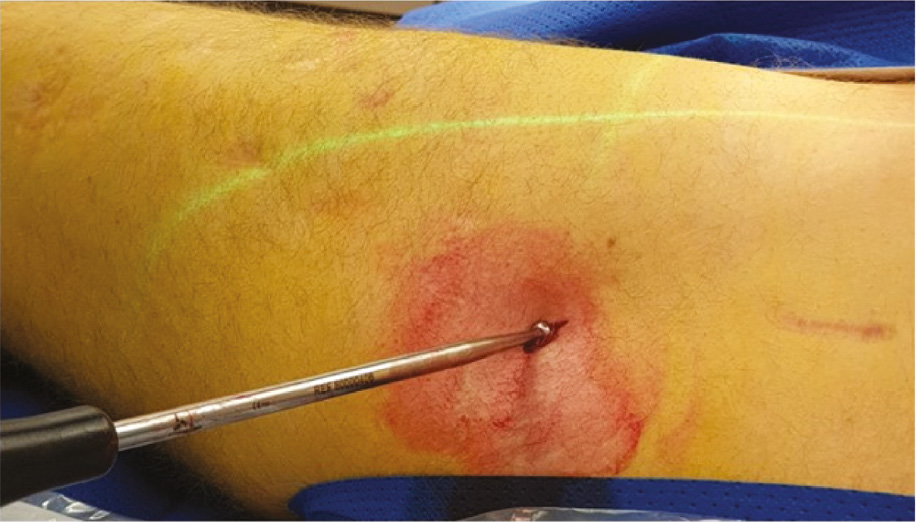

Figure 4. Rotate the limb until the distal interlocking elements are in perfect profile. This will help determine if there has been any bone growth over the top of the fixation elements that might preclude a percutaneous removal attempt. It is additionally advised to use this position to remove the screw. Placing the screwdriver in-line with the screw in perfect profile and perpendicular to the fluoroscopy beam will ensure proper orientation and facilitate engagement into the screw head.

jposna20220031_fig4.jpg